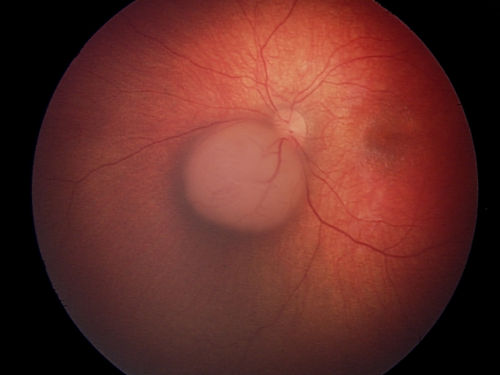

This is an EUA picture of retinoblastoma tumor group A. Tumor group A has very low risk of losing the eye. Group A includes small tumors located only in the retina; not near important structures.

Tumor Group A

The tumor is small and only in the retina. It is not near important eye structures.